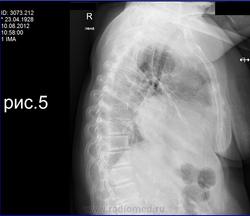

Больная - 88 лет с признакками застойной сердечной недостаточностью и патологией легких, которая не рассасывается на фоне АБТ.

Жидкость - транссудат. признаков системной воспалительной реации нет.

Заключение КТ-шников: секвестрация легких с воспалительными изменениями. КТ с контрастом.

Мне кажется, что есть образование средней доли, расширение корней и средостения влево, тяжистость в левом лёгком.

Я, кроме гидроторакса, больше ничего пока не вижу.

Секвестрация легкого - врожденный порок развития. Дайкомы КТ надо бы посмотреть. Или, хотя бы, скан протокола КТ.

аорта и ветви кальцинация стенок

Если жидкость транссудат, то ССН или цирроз печени.

Бронхоскопия? Интересуют изменения в среднедолевом бронхе. Такой массивный выпот слева с частичным осумкованием - пункции не до конца выполнены, остается не меньше литра жидкости слева. Нижняя доля слева компрессирована выпотом. Нормальное разделение ветвей легочной артерии и легочных вен, насколько можно судить по видео... Признаков аномального дренирования, дополнительных артериальных веточек, характерных для секвестрации, я не нашла. Узелок в S10 справа очень подозретильный на мтс. Общее впечатление - онкология. Но указать пальцем, где она - не могу. Дайкомы нужны.